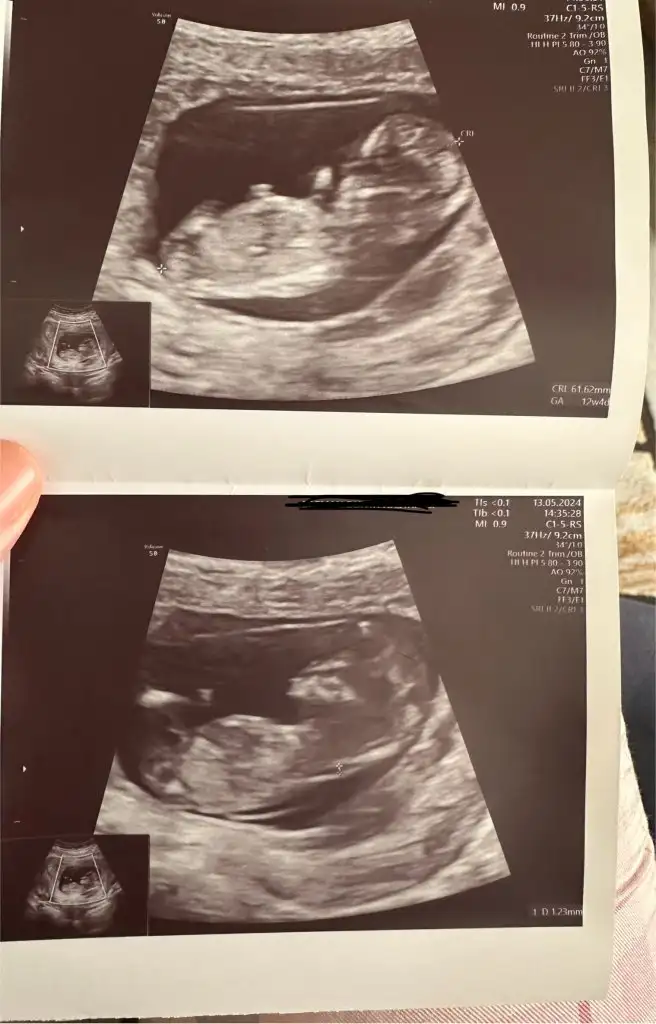

Merhaba bana da tahminde bulunur musunuz?? 12+2 haftalık

Eklentiler

• IMG_8136.webp

34,1 KB · Görüntüleme: 127